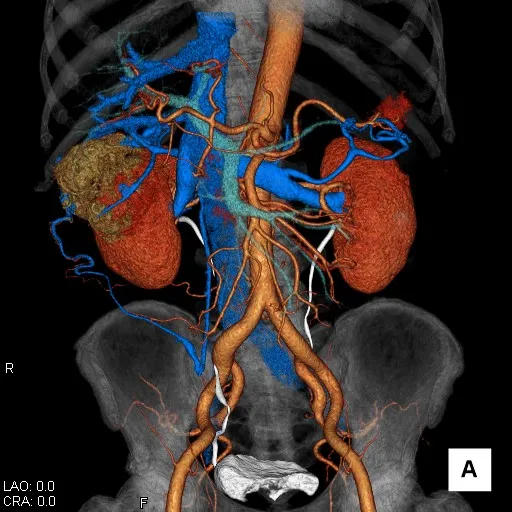

腎臓造影CT検査 3D画像